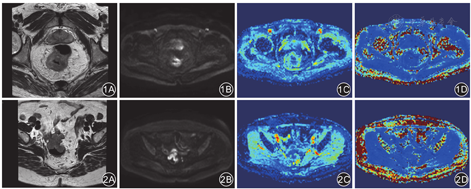

167例直肠腺癌患者中,野生型组(TA6/6)患者的ADC、MD值均明显高于突变型组患者(TA6/7与TA7/7),而MK值明显低于突变型组患者,差异有统计学意义(P值均< 0.01),见表1。典型病例见图1、图2。

应用Matlab软件(美国MathWorks公司)对DKI图像进行后处理,在b值为1 400 s/mm2的图像上,选择肿瘤截面最大的层面。参照常规T2WI图像,沿着肿瘤边缘勾出ROI,小心避开坏死及囊变区,计算DKI参数平均弥散系数(mean diffusivity,MD)、平均峰度系数(mean kurtosis,MK)以及ADC值,同时生成对应参数的伪彩图。参数ADC的计算使用了单指数模型。由2位工作5年以上的影像科医师在不知道UGT1A1*28基因检测结果的情况下独立完成,并取两者的平均值进行分析。